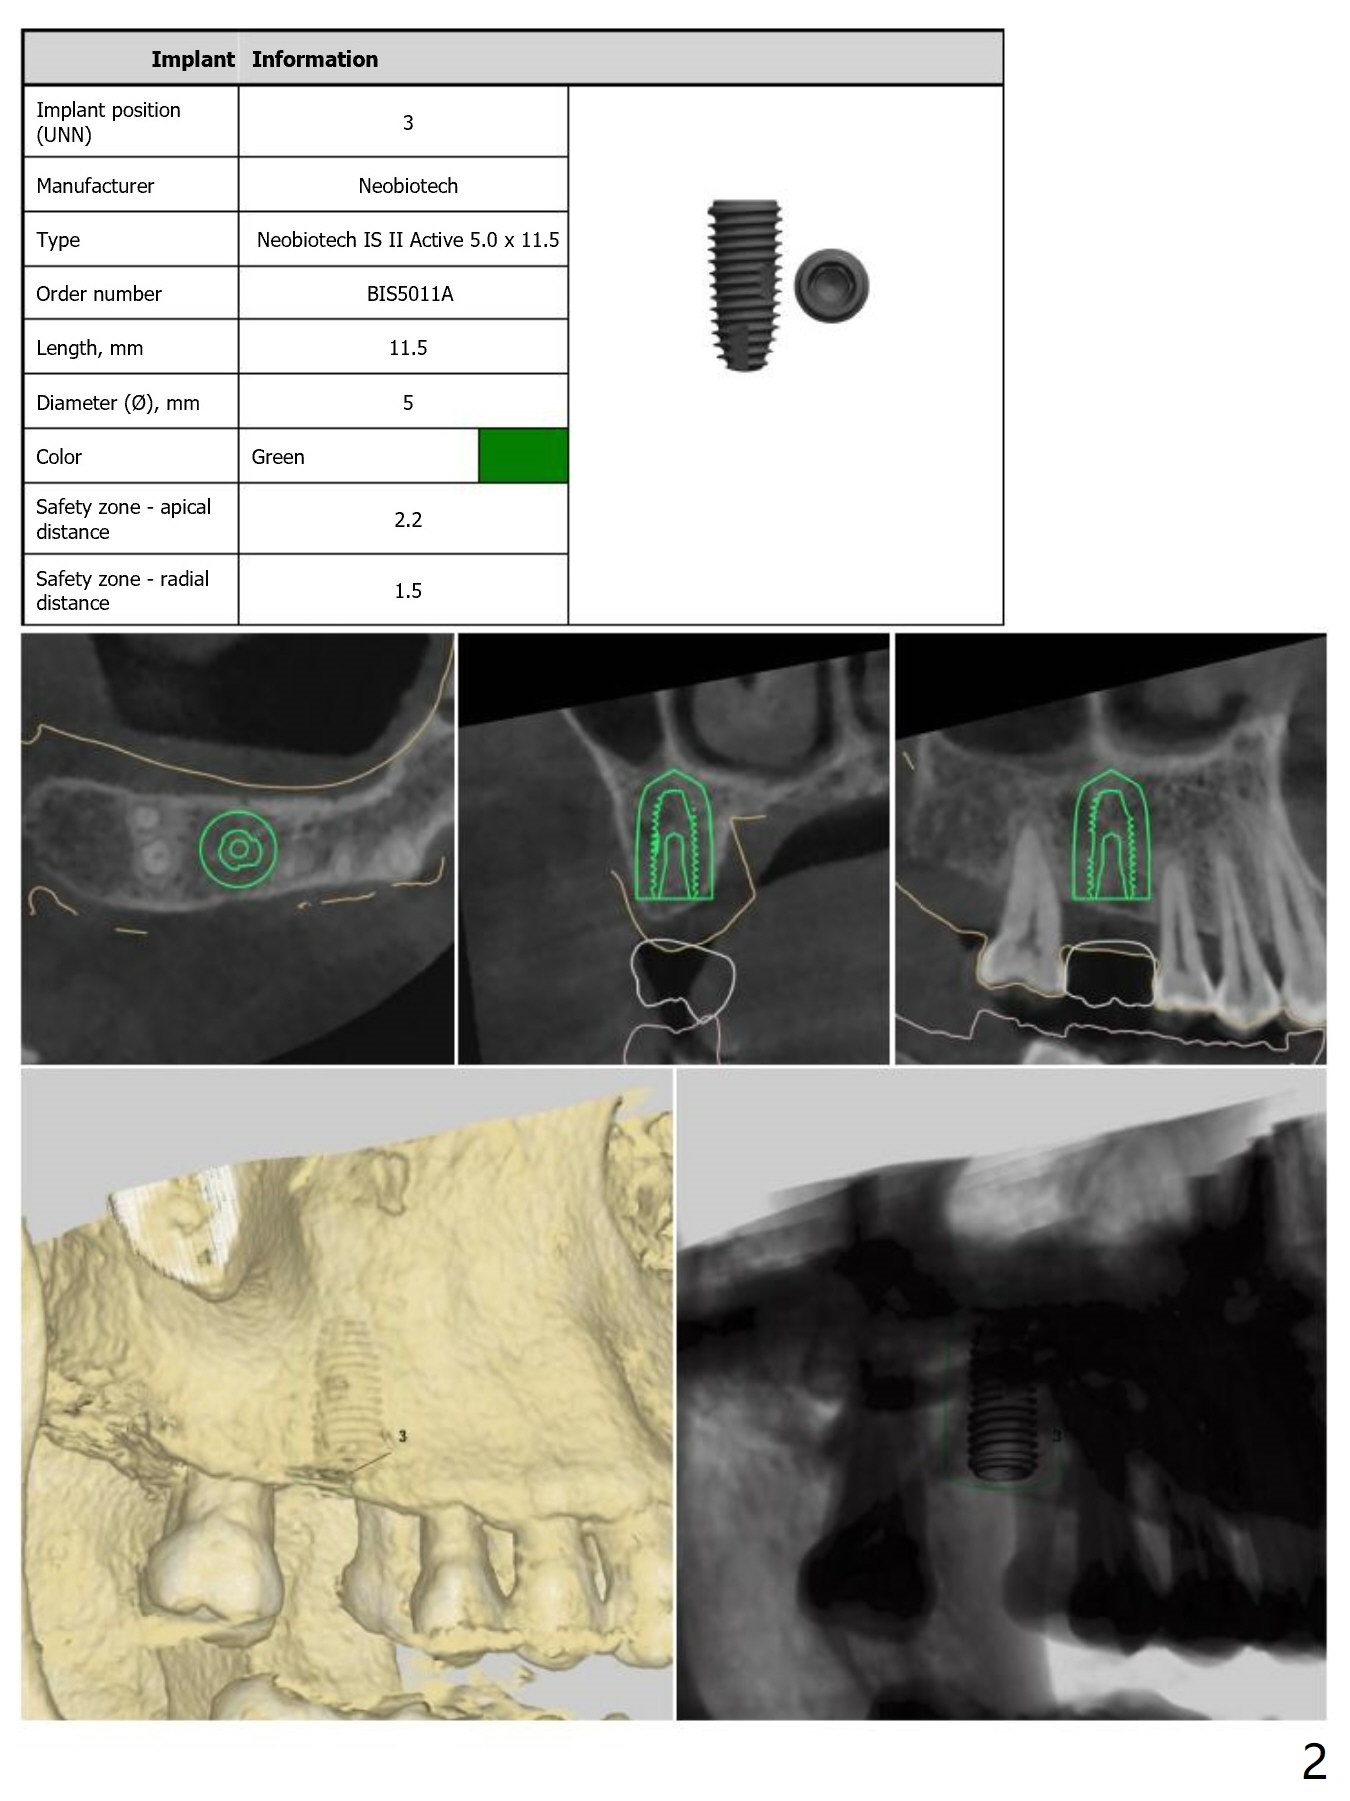

No Sinus Lift Required.  Undersized Drilling with No Tapping

Return to Upper Molar Immediate Implant, Armaments

Xin Wei, DDS, PhD, MS 1st edition 04/08/2018, last revision 09/07/2018